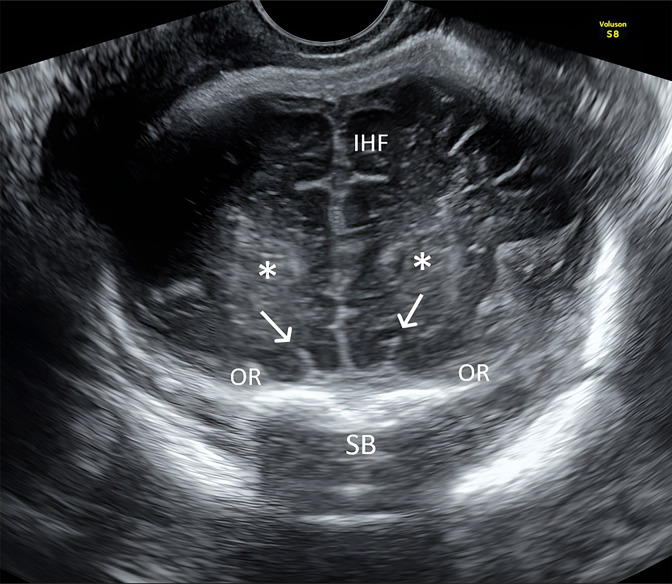

Methods: We prospectively evaluated OS development in fetuses diagnosed with CHDs from 2017 to 2021. Neurosonography was performed using transabdominal and transvaginal approaches after 30 weeks of gestation. OS assessment was conducted in the trans-frontal coronal plane, classifying their appearance as fully developed, hypoplastic, or absent. Abnormal OS cases underwent MRI and trio-based clinical exome sequencing (CES).

Results: The study included 147 fetuses with CHD. Abnormal OS were found in 4 fetuses (2.7%) which also exhibited other additional anomalies. OS were absent in cases 1-3 and hypoplastic in case 4. MRI confirmed OS abnormalities in all cases, and trio-based CES identified a CHD7 gene mutation in cases 1, 2, and 4, supporting the diagnosis of CHARGE syndrome. Case 3 had normal trio-based CES results. No other CHARGE syndrome cases were diagnosed postnatally among the cases with normal OS.